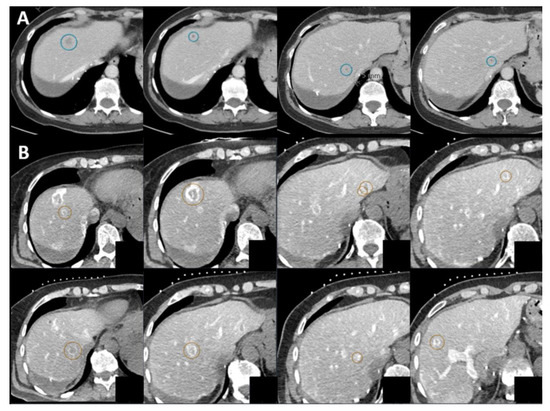

| Case No. | Tumor Size (mm) | Catheter Tip Position | Amount and Type of Contrast per Injection | Ablation Device | Institute |

|---|---|---|---|---|---|

| 1 | 20 mm | Common hepatic artery | 15–20 mL Visipaque™ | Emprint™ Microwave Ablation System, Medtronic-Covidien, Boulder, CO, USA | MD Anderson, Houston, TX, USA |

| 2 | 20 and 7 mm | Common hepatic artery | 4 mL Xenetix 300® | Cool-tip™ RFA Ablation Aystem, Medtronic-Covidien, Boulder, CO, USA | Gustave Roussy, Villejuif, France |

| 3 | 12 mm | Left-sided hepatic artery | Not specified | Cool-tip™ RFA Ablation System | Gustave Roussy |

| 4 | 9 mm | Common hepatic artery | 10 mL Xenetix 300® | Emprint™ Microwave Ablation System | Amsterdam UMC, Amsterdam, The Netherlands |

| 5 | 15 mm | Coeliac trunk | 20 mL Xenetix 300® | Emprint™ Microwave Ablation System | Amsterdam UMC |

| 6 | Not applicable | Common hepatic artery | 20 mL Xenetix 300® | Emprint™ Microwave Ablation System | Amsterdam UMC |

| 7 | Confluent | Common hepatic artery | 10 mL Xenetix 300® | NanoKnife system under ECG-gating; AccuSync model 72, AngioDynamics, Latham, NY, USA | Amsterdam UMC |

| 8 | 15 mm | Common hepatic artery | 15–20 mL Visipaque™ | Emprint™ Microwave Ablation System | MD Anderson |